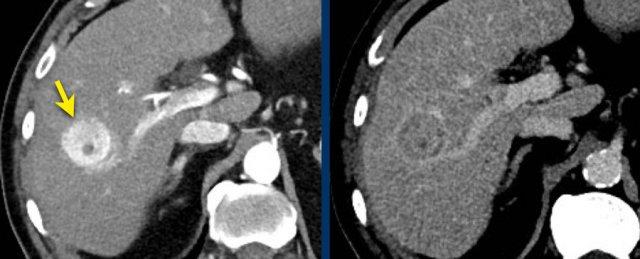

Các hình ảnh cho thấy một tổn thương ngấm thuốc động mạch dạng viền nhẹ ở phân thùy V có thải thuốc.

Có thể thấy một vùng giảm ngấm thuốc dạng tuyến tính kéo dài từ khối u, gợi ý khối u trong tĩnh mạch (mũi tên vàng).

Vì chúng ta không hoàn toàn chắc chắn đây là huyết khối do khối u, nên không thể phân loại trường hợp này là LR-TIV.

Một CT theo dõi được thực hiện, cho thấy tiến triển nặng của khối u cũng như xâm lấn mạch máu vào nhánh tĩnh mạch cửa phải trước (mũi tên trắng).

Lúc này chúng ta có thể xác định chắc chắn sự xâm lấn khối u vào tĩnh mạch cửa.